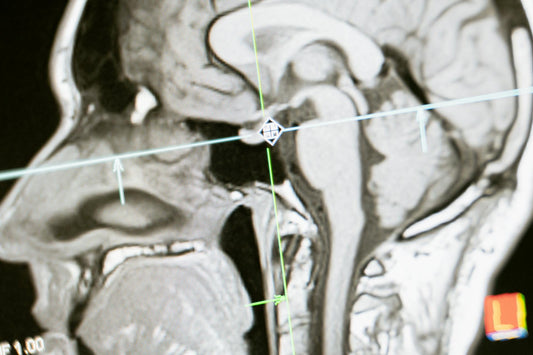

What is Dopamine Deficiency?

Dopamine Deficieny? What is it? What does a stupid molecule have anything to do with me relapsing? Learn about what this is and more here!